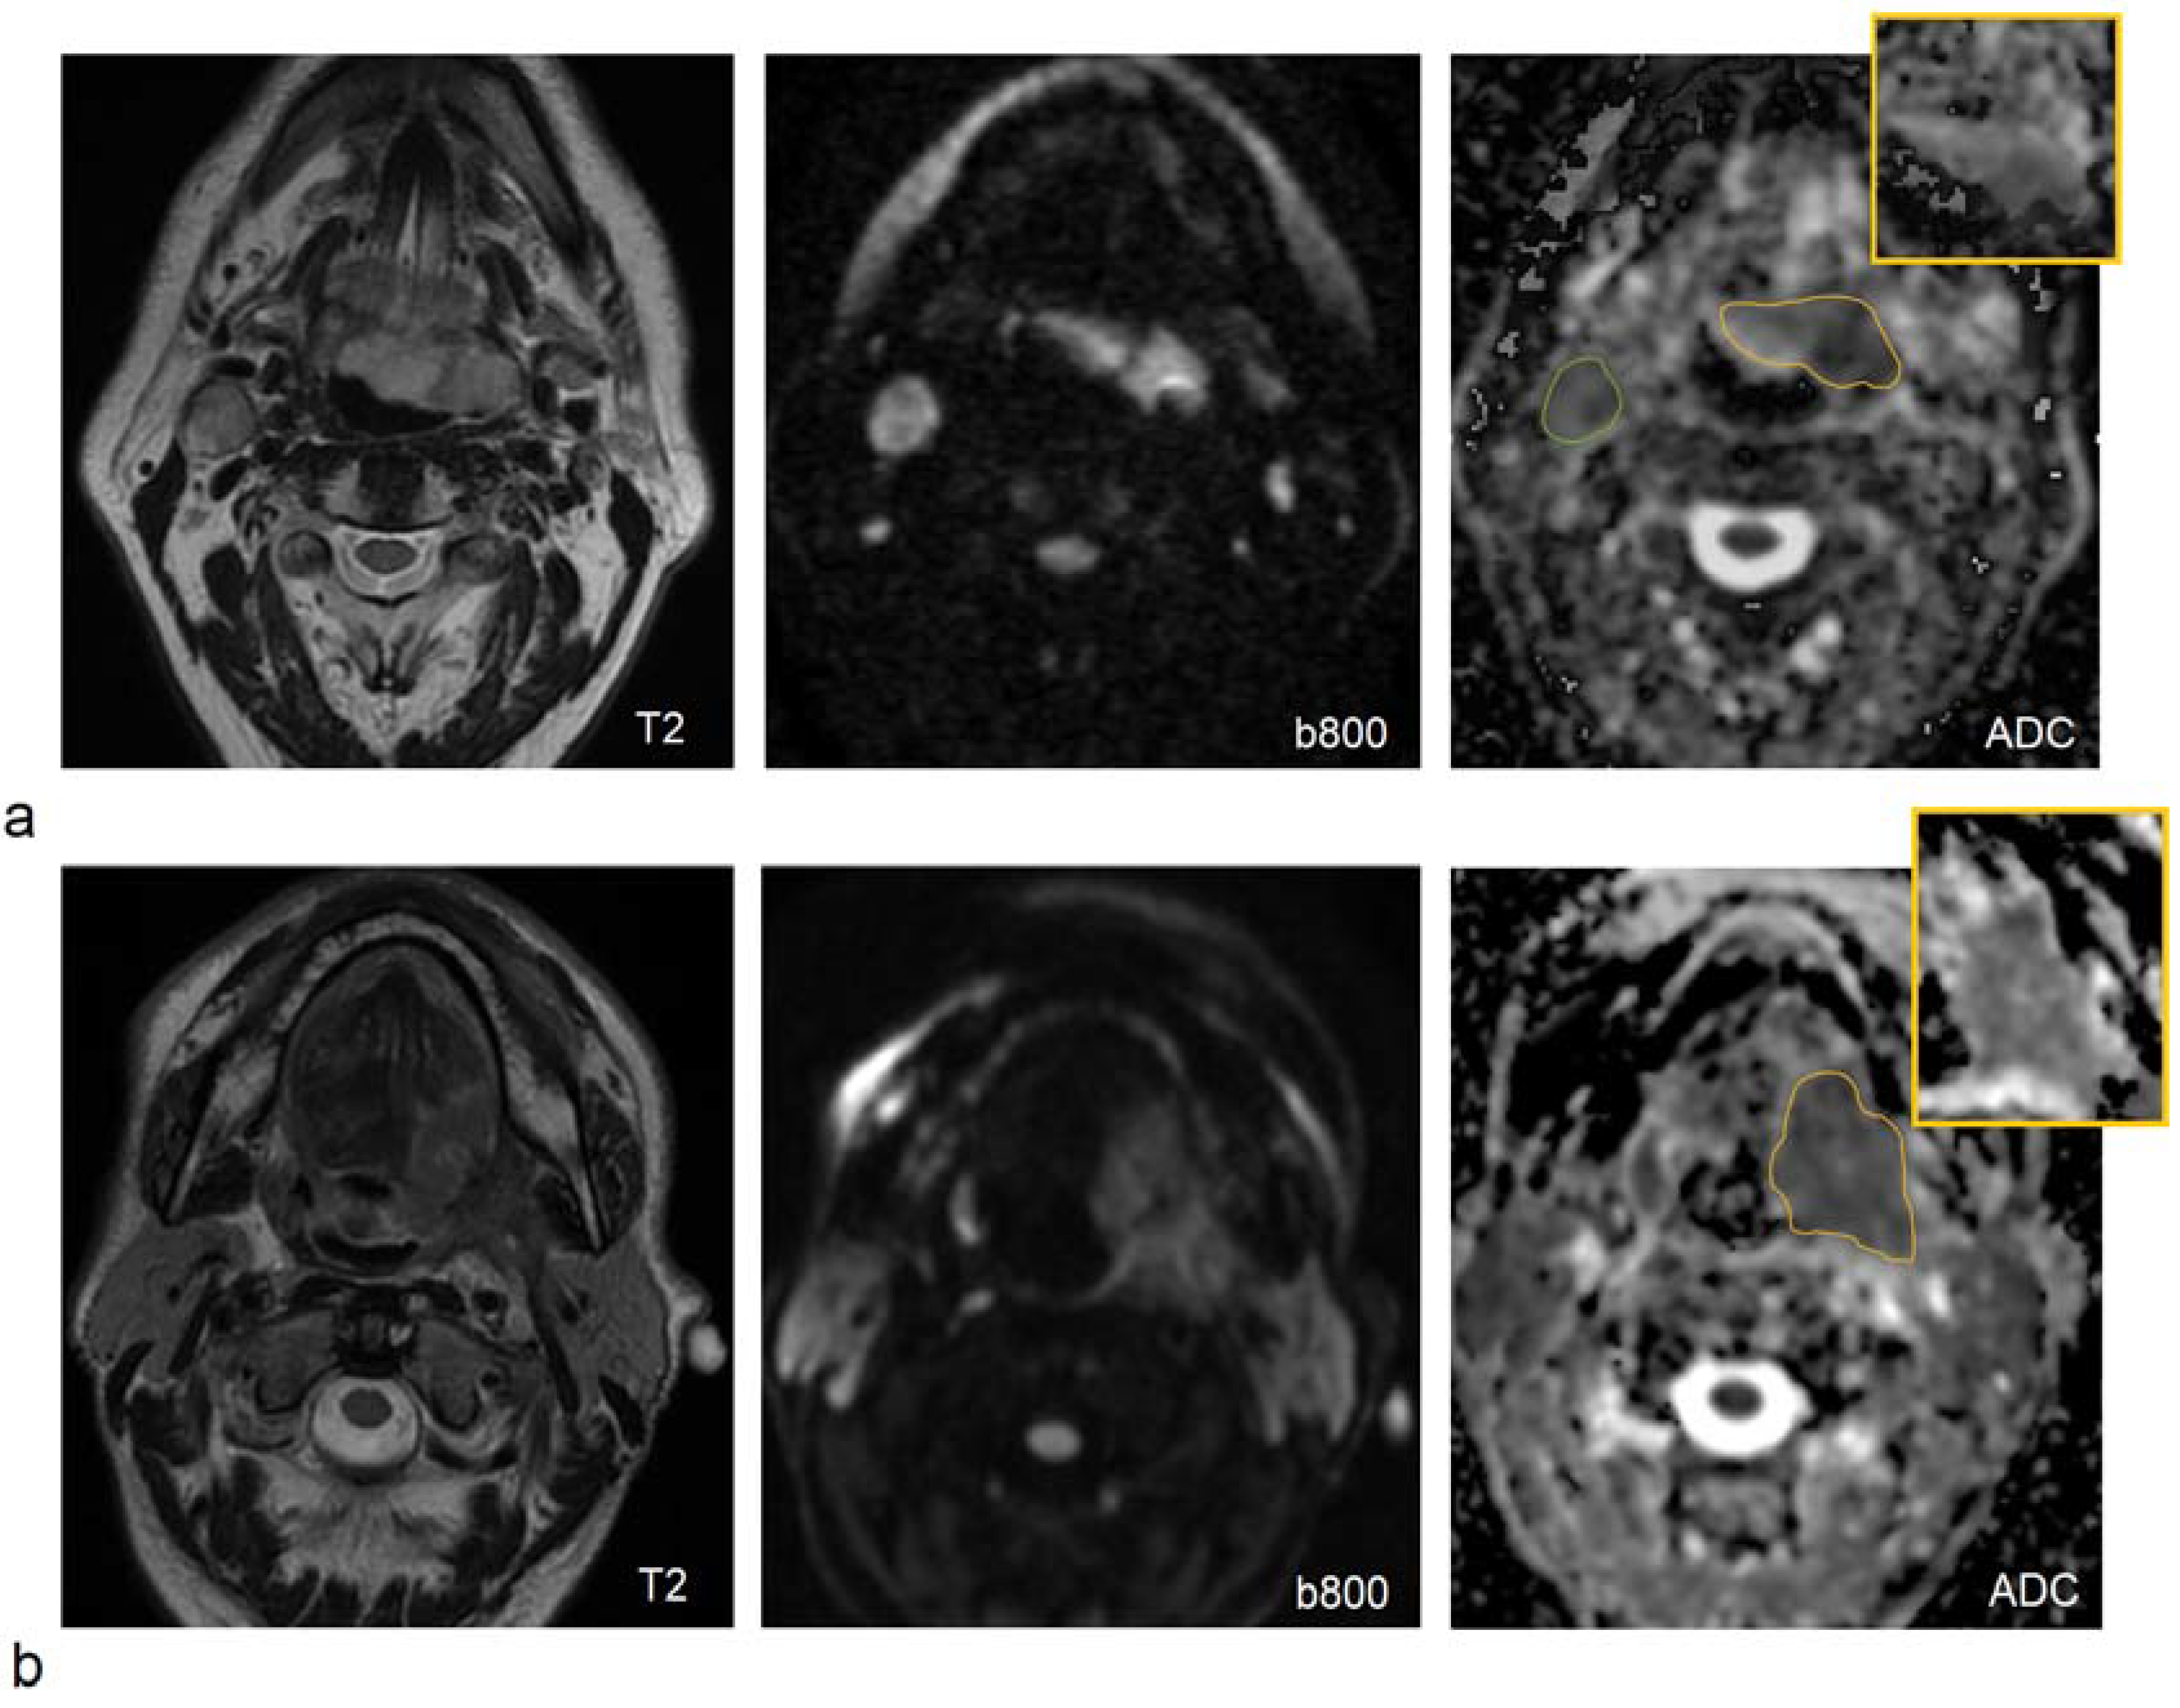

- Ravanelli, M.; Grammatica, A.; Tononcelli, E.; Morello, R.; Leali, M.; Battocchio, S.; Agazzi, G.M.; Buglione di Monale, E.; Bastia, M.; Maroldi, R.; et al. Correlation between Human Papillomavirus Status and Quantitative MR Imaging Parameters including Diffusion-Weighted Imaging and Texture Features in Oropharyngeal Carcinoma. AJNR. Am. J. Neuroradiol. 2018, 39, 1878–1883. [Google Scholar] [CrossRef]

- Vidiri, A.; Marzi, S.; Gangemi, E.; Benevolo, M.; Rollo, F.; Farneti, A.; Marucci, L.; Spasiano, F.; Sperati, F.; Di Giuliano, F.; et al. Intravoxel incoherent motion diffusion-weighted imaging for oropharyngeal squamous cell carcinoma: Correlation with human papillomavirus Status. Eur. J. Radiol. 2019, 119, 108640. [Google Scholar] [CrossRef]